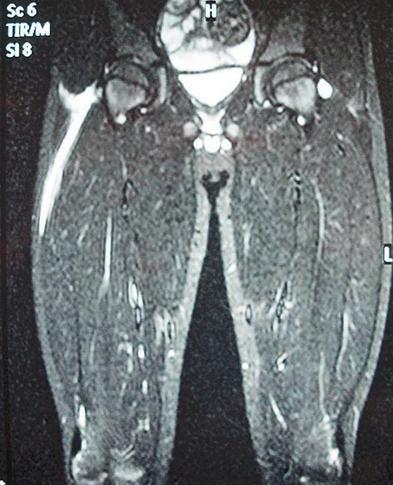

坏死性筋膜炎又称食肉菌感染,是一种广泛而迅速的皮下组织和筋膜坏死为特征的软组织感染,是一种非常罕见的感染性疾病。食肉菌专“吃”脂肪和筋膜,如果不及时清除,短时间内患者就会发展为中毒性休克、多器官功能衰竭甚至死亡。本病是多种细菌的混合感染,其中主要是化脓性链球菌和金黄葡萄球菌等需氧菌。本病感染只损害皮下组织和筋膜,不累及感染部位的肌肉组织是其重要特征。

(1)片状红肿、疼痛:早期皮肤红肿,呈紫红色片状,边界不清,疼痛。此时皮下组织已经坏死,因淋巴通路已被迅速破坏,故少有淋巴管炎和淋巴结炎。感染24h内可波及整个肢体。个别病例可起病缓慢、早期处于潜伏态势。受累皮肤发红或发白、水肿,触痛明显,病灶边界不清,呈弥漫性蜂窝织炎状。

(4)奇臭的血性渗液:皮下脂肪和筋膜水肿、渗液发黏、混浊、发黑,最终液化坏死。渗出液为血性浆液性液体,有奇臭。坏死广泛扩散,呈潜行状,有时产生皮下气体,检查可发现捻发音。